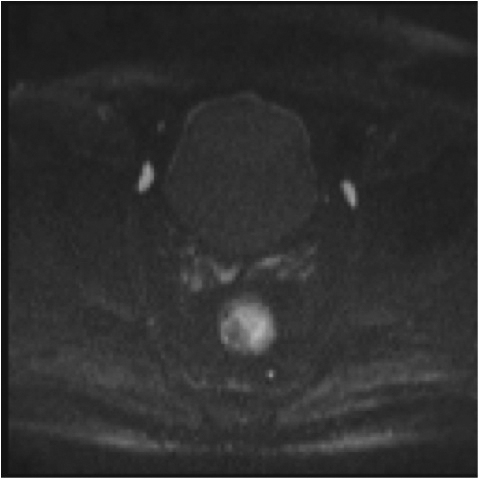

e,f) restricție de difuzie la nivelul tumorii rectale și a doi ganglioni mezorectali

Fig.2. Același pacient post chimio-/ radioterapie – răspuns complet cu dispariția masei tumorale rectale; dispariția restricției de difuzie și reducere în dimensiuni a ganglionilor mezorectali; pacientul a beneficiat de TME şi s-a confirmat histopatologic absenţa ţesutului tumoral (pT0 pN0).

e) difuzie RM (b1000)